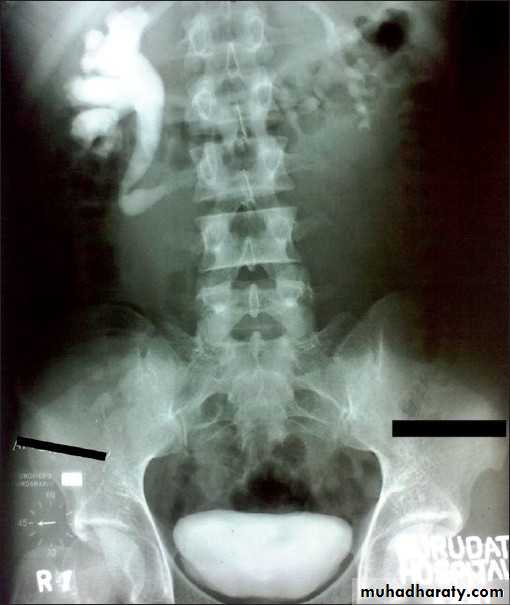

retrocaval ureter